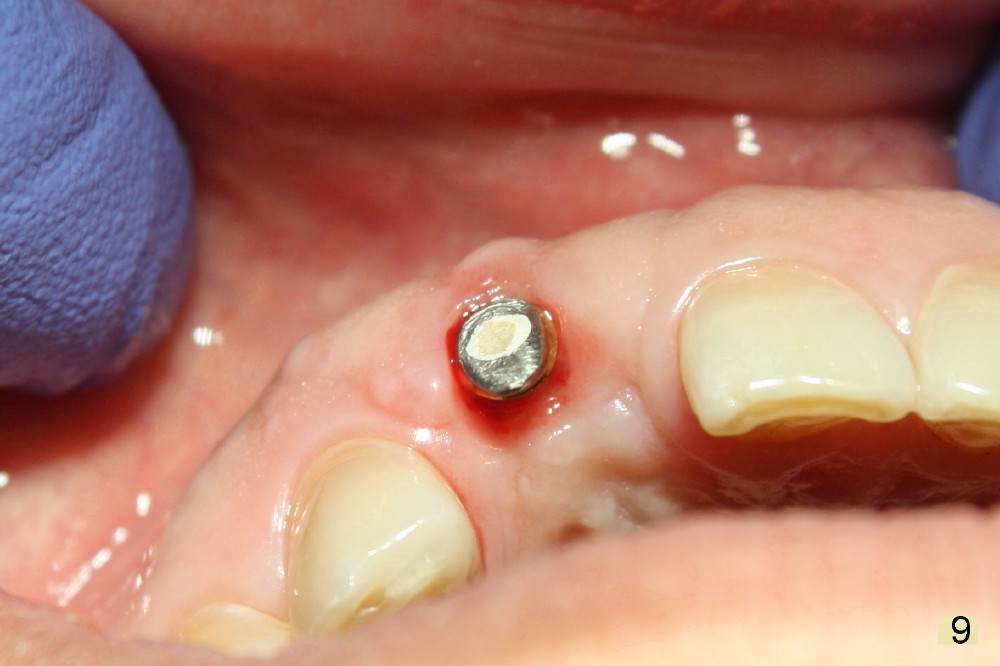

Fig.7,8 show the provisional 10 days and 1.5 months postop, respectively. When the provisional is removed, the implant/abutment is buccally malpostioned (Fig.9). It appears that segmental osteotomy is necessary. Fig.10 shows incision design. The implant and bone complex is to be moved to an ideal position (Fig.11,12). A block graft is inserted apically for internal fixation. An ortho wire is used for external fixation.